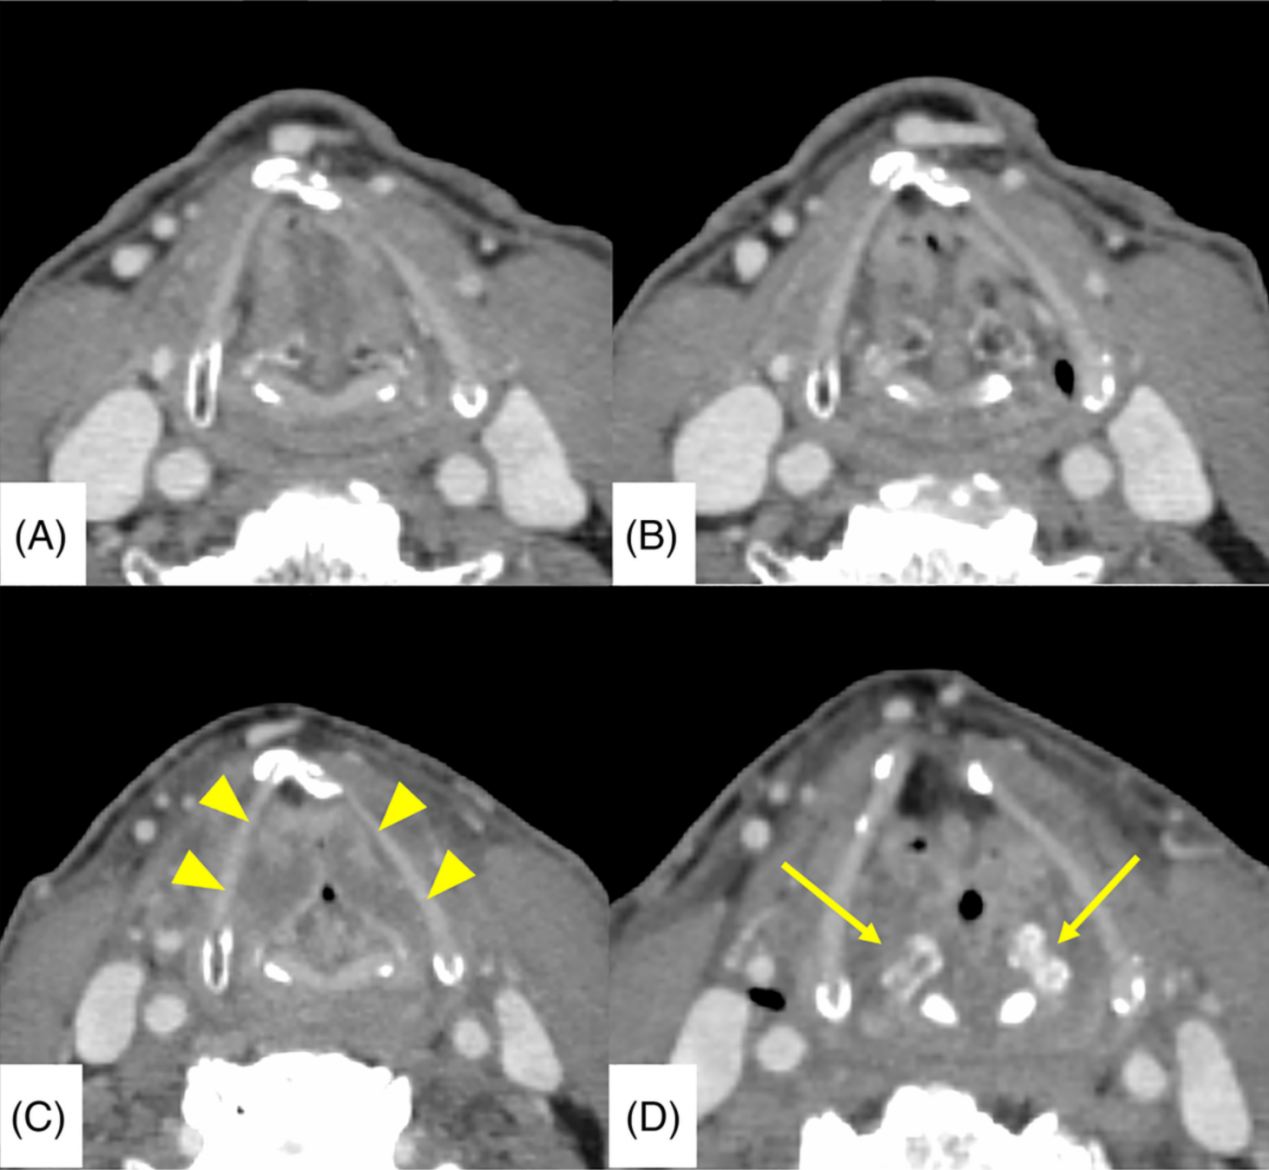

一名63岁男子出现持续6个月的声音嘶哑。喉镜检查发现右侧声带有白色病变(图1A)。对右侧声带进行活检,患者被诊断为声门型鳞状细胞癌。病人报告说40多年来每天1500毫升啤酒及一包半香烟。诊断时患者戒烟。

RT启动后3天,喉镜检查显示右侧声带原发肿瘤的大小略有增加(图1B)。RT开始2周后,患者恢复吸烟,喉镜检查结果显示双侧声带粘膜有轻微改变,伴有白色病变(图1C)。他被指示再次戒烟。然而,他继续在RT期间每日饮用1500毫升啤酒。RT按时完成,无中断(总治疗时间为42 天)。RT完成时,喉镜检查显示原发肿瘤已消失(图1D)。急性并发症包括2级皮炎和1级粘膜炎。初始治疗反应为完全缓解(CR),并开始随访。

每月进行一次检查,RT后1年未观察到局部复发或转移(图1E)。在随访期间,尽管患者已戒烟,但他仍继续饮酒 。 RT后13个月,患者恢复每天一包香烟。在恢复吸烟一个月后,喉镜检查显示双侧声带轻微改变,伴有白色病变(图1F)。

在恢复吸烟2个月后,出现了严重的咽痛和声音嘶哑。喉镜检查发现喉部有一肿物(图3A),当时没有进行CT检查。11天后,手术切除肿物(图3B),组织学诊断为放射性喉坏死,为晚期毒性,无癌症复发(图4)。

手术切除后,尽管口服止痛药,患者仍持续出现咽痛。术后3周,患者突然出现呼吸困难,喉镜检查结果显示完全性喉麻痹(图3C)。病人接受了紧急气管造口术。气管切开后,持续的咽痛暂时消失。增强CT显示双侧声带水肿,双侧杓状软骨萎缩及硬化(图5)。增强CT检查未发现癌症复发。

经静脉注射类固醇后喉镜检查结果显示声带运动和坏死略有改善(图3D),随后改用口服泼尼松龙,进一步改善了喉坏死和喉麻痹(图3E)。患者出院2周后(气管造口术后1个月),喉镜检查结果显示双侧声带进一步改善,与气管造口术前状态相似(图3F)。气管孔阻塞后也未观察到呼吸窘迫。